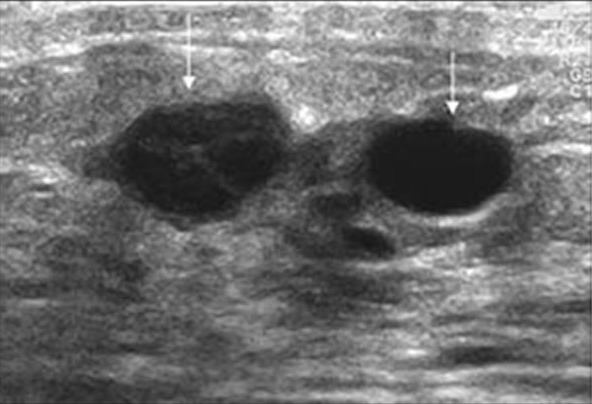

Mammogram images: Normal, abnormal, and breast cancer

breast cancer on ultrasound looks like Mammogram images: Normal, abnormal, and breast cancer